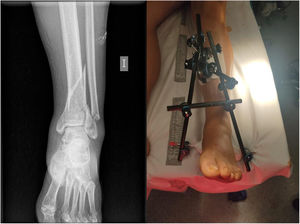

Of the total of 178 contusion patients, 107 fractures were recorded, of varying severity (60.1%), 3 of these open (2.8%): 2 open type II Gustilo and Anderson fractures of the third phalanx of the 3rd finger of the right hand, treated conservatively; an open type II fracture of the distal third of the left tibia requiring damage control surgery with closed reduction and external fixation (Fig. 3). The most frequent fractures were those related to segment 44 (distal tibia–fibula) according to the AO classification, with a total of 17 (15.9%); then 15 (14.1%) distal radius fractures; followed by segment 31 fractures (11.2%), with a total of 12, where the most frequent was the unstable pertrochanteric fracture (31-A21), with statistically significant differences (p<0.05).

A systematic review by Saulnier et al.12 in 2017 found that very few studies had investigated injuries caused specifically by floods, however it is known that injuries such as sprains (14.4%), non-specific pain (5.6%) and dislocations (2.4%) require conservative treatment in almost all cases. In our population, there was only one case of native posterior dislocation of the hip, with a 48-h evolution, which required closed reduction under sedation in the operating theatre (Fig. 5).

Social pressure and the fear of contamination or poisoning due to wounds increased the number of patients treated in the following days. A total of 84 wounds were recorded, the treatment carried out on them being modified over the course of the events. Following interhospital consensus between the centres serving the affected populations and in accordance with the antibiotic management protocols used individually by each hospital, the initial intravenous antibiotic combination was piperacycline–tazobactam (4g/6–8h)+linezolid (600mg/12h). This treatment was of choice for those who had been contaminated and whose wound had exceeded 6h of evolution. Of the total number of wounds, 6 debridements were required (7.1%) and a total of 15 wounds (17.8%) required associated negative pressure therapy (Fig. 6).